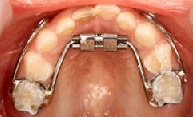

ハイラックス(急速拡大装置)

「ハイラックス」は、上アゴの歯列と歯を支えているアゴの骨を拡大させるための装置です。

中央にあるネジを少しずつ回転させることにより、上顎骨(鼻上顎複合体)の成長(側方、前方)を促進させます。

●パラィティタイプ

装着時

使用中